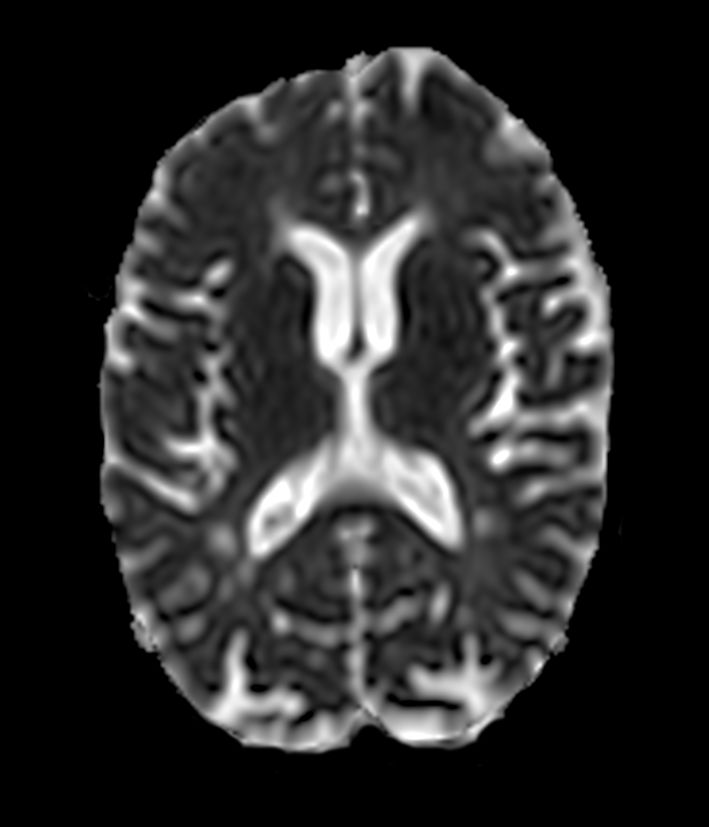

DWI b1000

DWI b1000 (ADC)